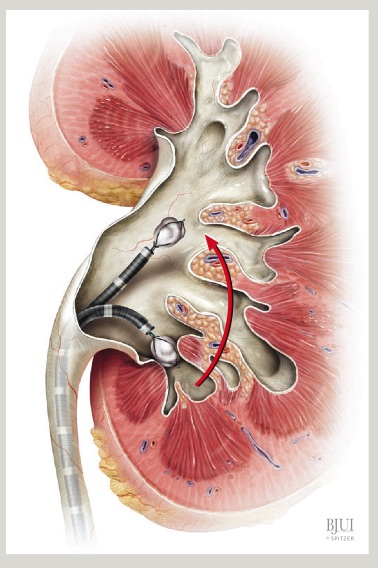

La cirugía se inicia con la instalación de un catéter ureteral externalizado. Éste permite contrastar la vía urinaria superior e identificar en la fluoroscopía, la pelvis y los cálices del riñón a tratar. Posteriormente se realiza una punción renal bajo rayos y/o dirigida por ecografía, hacia la papila renal del cáliz escogido para ingresar. Obtenido este acceso, se avanza una guía hidrofílica y se procede a la dilatación del trayecto percutáneo, lo que permitirá la instalación de una camisa (amplatz) que comunicará la piel con el cáliz y dará acceso al nefroscopio, equipo operado por el urólogo para la fragmentación y extracción de la litiasis a tratar.